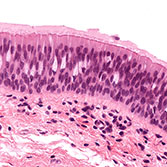

Histology is the study of the microanatomy of cells, tissues, and organs as seen through a microscope. It examines the correlation between structure and function.

Histology Guide teaches the visual art of recognizing the structure of cells and tissues and understanding how this is determined by their function. Rather than reproducing information found in a histology textbook, a user is shown how to apply this knowledge to interpret cells and tissues as viewed through a microscope.

An Aperio slide scanner was used to obtain a high-resolution image of each slide in its entirety. Large tissues are up to 34 GB for a single, uncompressed image of 150,000 x 75,000 pixels.

The contrast, color, and sharpness of each image were adjusted to at least maintain the appearance of the tissue as seen through a microscope. In many cases, these adjustments improved upon their visual appearance.

Unlike low-resolution images, users can interactively explore these large images by zooming-and-panning in real-time. A software-based virtual microscope (Zoomify HTML5 Enterprise) allows the examination of large and small structures in the same specimen.